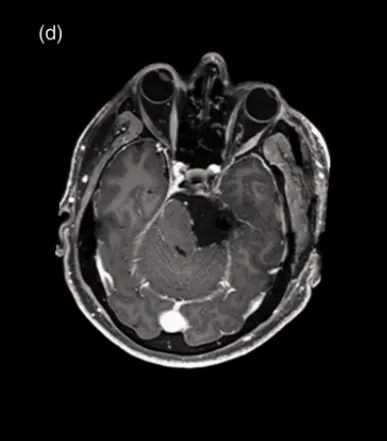

这是一名53岁的男性患者,因罹患大型天幕脑膜瘤(体积为27 cm³),为寻求手术治疗而入住法国巴黎Lariboisiere大学医院,向INC国际神经外科医生集团旗下世界神经外科顾问团(WANG)成员、世界神经外科联合会(WFNS)颅底手术委员会前主席Sebastien Froelich教授(塞巴斯蒂安·福洛里希教授,福教授)求诊。

MR显示,肿瘤起源于天幕并向岩斜坡延伸,界限清晰,为轴外肿瘤,明显压迫脑干,瘤周无水肿,均匀增强强化,支持脑膜瘤的初步诊断。